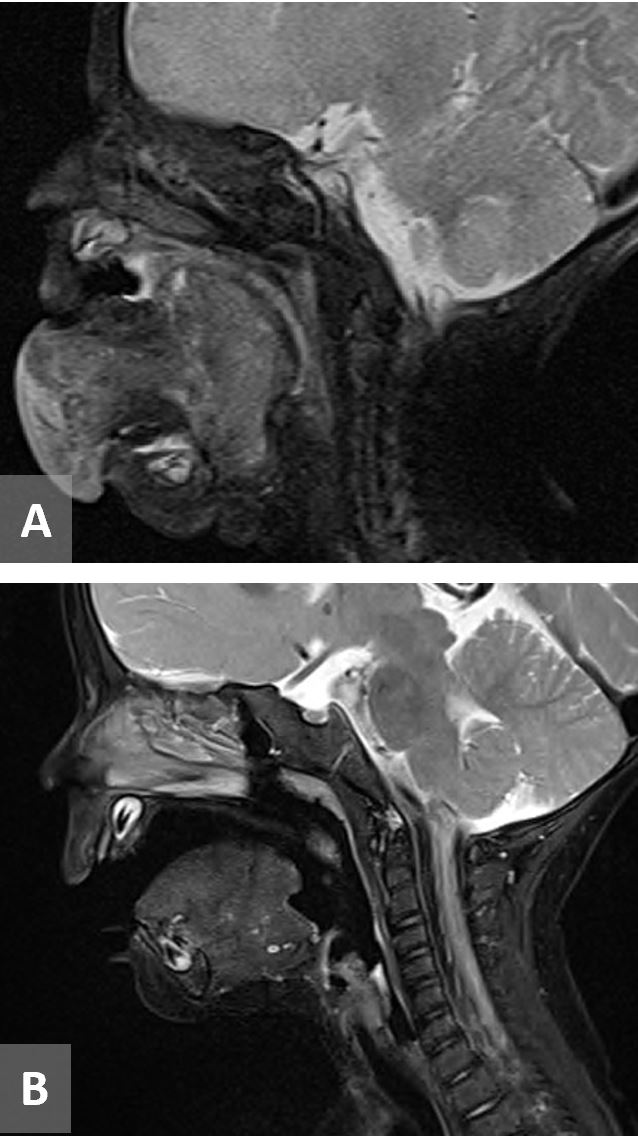

The patient then underwent transnasal intubation in the operating room and magnetic resonance imaging (MRI). MRI face with and without contrast showed a large mass that filled and distorted the normal anatomy of the oral cavity and floor of mouth with extent inferiorly and laterally to the level of the mandible without bony extension and superiorly to the level of the hard palate and posteroinferiorly to the vallecula, measuring 3.4 x 5.5 x 3.1 cm. The mass was isointense to soft tissue on T1 and heterogeneously hyperintense on T2 with absence of vascular flow voids (Figure 2). MRI brain was noted to be normal.

Figure 2. (A) MRI T2 sequence showing a large tongue mass that is heterogeneously hyperintense without vascular flow voids measuring 3.4 x 5.5 x 3.1 cm. (B) MRI T2 sequence 5 months post-treatment. MRI, magnetic resonance imaging.